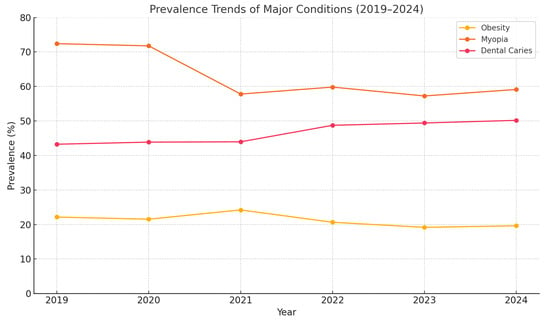

Background: Health issues among school-age children have emerged as a global public health concern. These conditions often do not occur in isolation but tend to cluster, indicating a widespread issue of multimorbidity among this population. This study examined the prevalence and clustering of

Background: Health issues among school-age children have emerged as a global public health concern. These conditions often do not occur in isolation but tend to cluster, indicating a widespread issue of multimorbidity among this population. This study examined the prevalence and clustering of multimorbidity among school-aged school students in the Yangzhou district. Methods: A repeated cross-sectional analysis was conducted from 2019 to 2024, including 22,512 students aged 6–18 years. Common diseases, under national key monitoring, including myopia, dental caries, obesity, elevated blood pressure, and growth disorders, were assessed. Multimorbidity patterns were identified using association rule mining (Apriori algorithm) with predefined thresholds (support ≥ 2.0%, confidence ≥ 20.0% and lift > 1). Results: The multimorbidity prevalence among school-age students in the Yangzhou district is 53.95%. The most frequent multimorbidity was found in dental caries and myopia, while the most common ternary pattern was found in obesity, dental caries, and myopia. The following gender differences were observed: boys had a higher multimorbidity prevalence (56.4%) compared to girls (51.2%), with boys more likely to exhibit obesity and dental caries, while girls showed a higher prevalence of myopia-related multimorbidity. By educational stage, primary school students showed a multimorbidity rate of 50.3%, junior high showed a rate of 54.6%, and senior high showed a rate of 57.9%, indicating a rising trend across age groups. Patterns of multimorbidity varied but were interrelated. Conclusions: From 2019 to 2024, the prevalence of multimorbidity among school-aged children in Yangzhou remained relatively high, primarily manifesting as co-occurring myopia and other health issues. Patterns of multimorbidity across gender and educational stage varied but were interrelated.

Figure 1